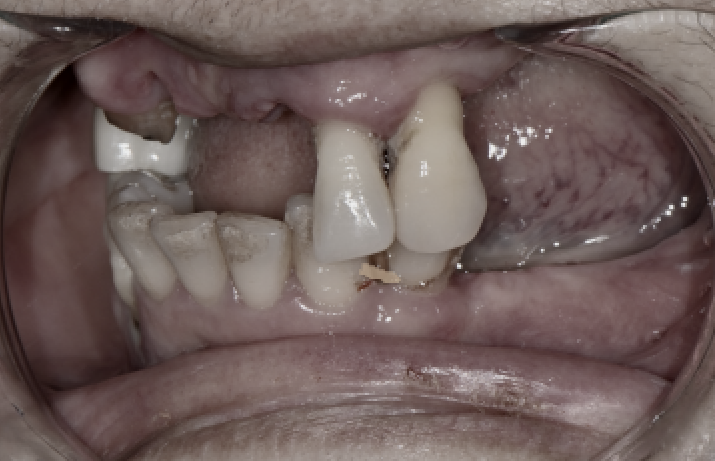

처음 내원하셨을 때의 상태

전체임플란트 전

환자분은 앞니·어금니 여러 부위가 약해져 있었고,

남아 있는 치아 또한 흔들리거나 깨져

기능을 거의 하지 못했습니다.

특히 어금니가 이미 빠져 있는 부위가 많아서

부드러운 음식 외에는 섭취가 어려운 상태였습니다.

발치 + 임플란트 식립, 한 번에 진행

서울오브치과병원 임플란트

오래된 보철물과 약해진 치아들을 발치한 뒤,

필요한 부위에 임플란트를 바로 심었습니다.

뼈가 부족한 부위는 GBR로 보완해 안정적으로 지지할 수 있도록 했습니다.